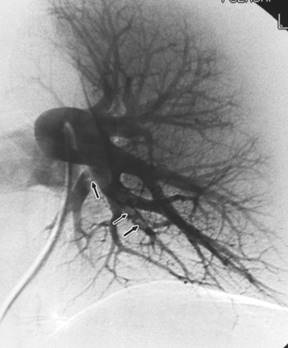

63-летний мужчина с одышкой на протяжении 24 часов. Дефекты в ветвях левой нижней доли левого лёгкого (указано стрелками) свидетельствуют об острой эмболии.

Рис. 5

При тромбоэмболии легочных артерий ангиопульмонографию выполняют экстренно на фоне интенсивных реанимационных мероприятий. При общей ангиопульмонографии рентгеноконтрастный препарат вводят (чаще через катетер) в верхнюю полую вену, правые предсердие и желудочек либо через локтевую, подключичную и бедренную вены с той или другой стороны. При селективной ангиопульмонографии под контролем рентгенотелевидения катетер проводят по нижней (через бедренную вену) или верхней (через вены верхней половины тела) полым венам, правому предсердию и желудочку в легочный ствол, куда и вводят рентгеноконтрастный препарат. Катетер может также быть введен в правую или левую легочную артерию и в сосуды меньшего порядка. При ангиопульмонографии при необходимости выполняют лечебные процедуры, например через катетер удаляют тромб легочной артерии или размягчают его ферментами.